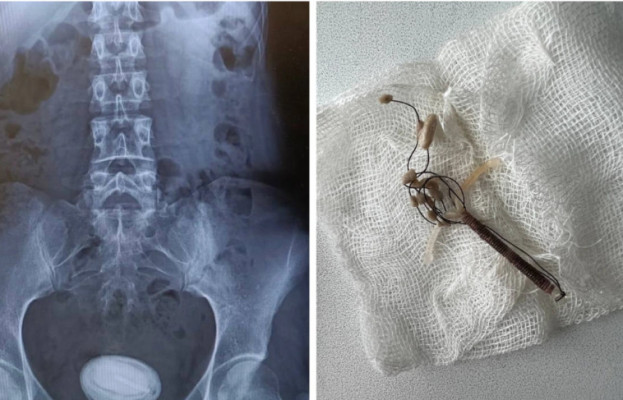

Жінка 25 років звернулась у Тернопільську міську комунальну лікарню швидкої допомоги зі скаргами на хронічний цистит, який постійно загострювався.

Лікар уролог призначив детальне обстеження для встановлення причин такої патології. Під час УЗД у сечовому міхурі було виявлено нетиповий великий утвір розміром 5.5 на 4.5 сантиметри. Про це розповіли на сторінці медичного закладу у фейсбуці.

В ході збору анамнезу, стало відомо, що 5 років тому пацієнтці було встановлено внутрішньоматкову спіраль. Через три роки на огляді у лікаря гінеколога її не вдалось замінити, оскільки вона була відсутня. Медик зробив висновок, що спіраль непомітно випала.

Було проведено додаткові обстеження, зокрема рентгенографію та цистоскопію, які остаточно підтвердили, що даний «камінь» насправді був протизаплідною спіраллю, яка потрапила в порожнину сечового міхура та вкрилась шаром камʼяних відкладень.

Лікарі урологи Михайло Балабан та Назарій Чернюк КНП «Тернопільська міська комунальна лікарня швидкої допомоги» провели малоінвазивну хірургічну операцію, під час якої вони без розрізів роздробили камінець та вилучили його, а також видалили спіраль з сечового міхура.